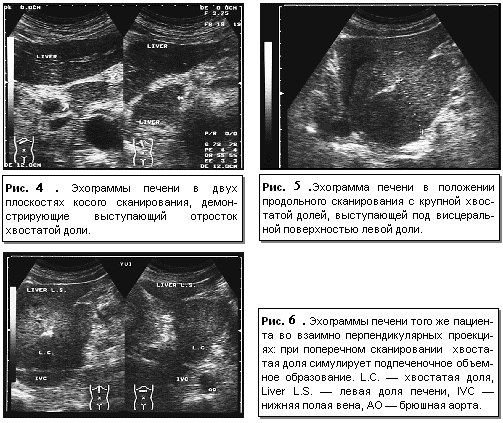

Анатомическими ориентирами границ между долями, выявляемыми при эхографии, служат: между правой и квадратной долями – ложе желчного пузыря; между квадратной и левой долями – круглая связка и борозда круглой связки; между квадратной и хвостатой долями – ворота печени; выемка венозной связки в виде гиперэхогенной перегородки (удвоенный листок капсулы и жировая клетчатка) – между левой и хвостатой долями. Хвостатая доля имеет в той или иной степени ярко выраженный хвостатый отросток, располагающийся на эхограммах кзади от ворот печени, кпереди от нижней полой вены и в латеральном направлении от основной массы хвостатой доли. Причем при достаточно больших размерах хвостатый отросток может значительно выступать со стороны висцеральной поверхности печени (рис. 4, 5 ,6).